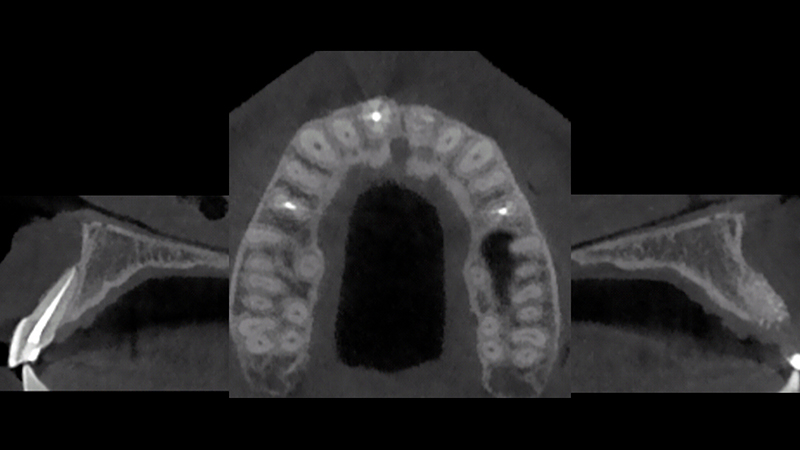

CBCT dopo 5 mesi

Fig. 10c - CBCT dopo 5 mesi.